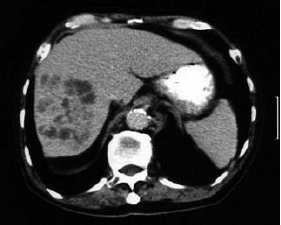

Um homem de 65 anos apresenta febre, astenia, perda de apetite, náusea e emagrecimento há cerca de 3 semanas. Os exames laboratoriais revelaram Htc 30%, Hgb 10g%, Leucócitos 11000 (0 – 0 – 0 – 0 – 7 – 68 – 17 – 8), AST 29 U/L (normal até 31 U/L), ALT 30 (normal até 37 U/L), fosfatase alcalina 320 U/L (normal até 120 U/L), bilirrubina total 0,9 mg/dL, bilirrubina indireta 0,7 mg/dL. USG abdominal: massa heterogênea de limites pouco definidos em lobo direito do fígado. TC de abdômen (a seguir). Observe as imagens e assinale a alternativa que apresenta o diagnóstico provável.